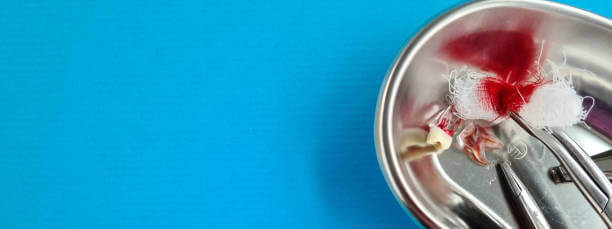

드라이소켓은 사랑니 발치 후 제대로 치유되지 않아 붓거나 염증이 발생하면서 통증이 나타날 수 있습니다. 사랑니 발치 후의 대표적인 부작용으로는 상처 치유 과정에서 혈전이 제대로 형성되지 않거나, 형성되더라도 3일 이내에 제거되어 사랑니 아래 잇몸뼈가 그대로 노출됩니다.

잇몸이 노출되면 입안에 남아있던 세균이 침투해 염증을 일으켜 심한 통증을 유발할 수 있습니다. 또한 잇몸의 경우 다른 신체 조직과 달리 딱지가 한번 빠지면 다시 형성되기 어려우므로 사랑니 발치 후 드라이소켓이 의심된다면 빠른 시일 내에 치과에서 봉합하는 것이 필요합니다.